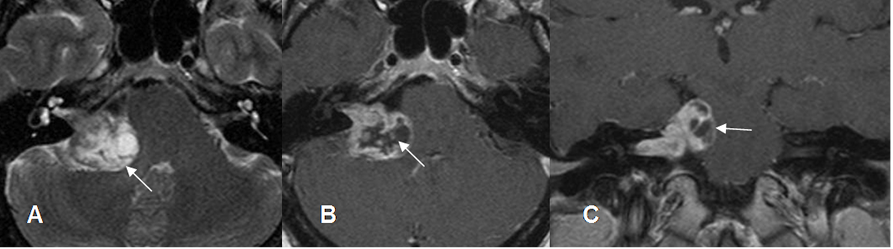

Fig 183. Neurofibroma acústico.

A: RM axial en T2. Lesión heterogénea en el ángulo pontocerebeloso, con extensión al CAI.

B: RM axial en T1 y C: RM coronal en T1 con contraste. La imagen realza de forma periférica, correspondiendo a un neurinoma del complejo VII-VIII par.